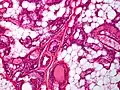

.jpg.webp) Small vessels in adipose tissue

Small vessels in adipose tissue.jpg.webp) Small vessels in adipose tissue

Small vessels in adipose tissue Small vessels in adipose tissue

Small vessels in adipose tissue Small vessels in adipose tissue

Small vessels in adipose tissue The vessels typically contain hyaline or fibrin (pictured) thrombi[4]

The vessels typically contain hyaline or fibrin (pictured) thrombi[4]